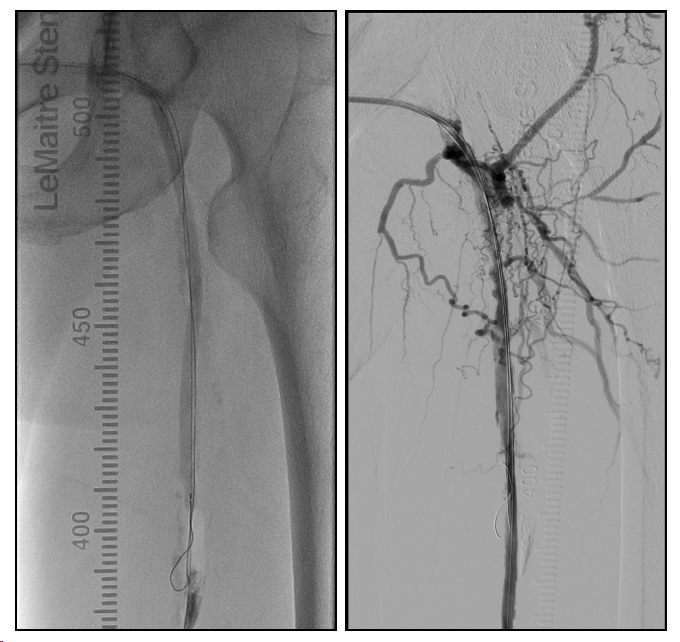

患者平卧位,局麻后顺行穿刺左侧人工血管植入6F 45cm鞘,造影提示人工血管吻合口远端股总动脉短段闭塞、股浅动脉长段闭塞、股深动脉开口闭塞(图6-7)。

(图6)术前造影,可见人工血管吻合口远端股总动脉、股深动脉开口、股浅动脉闭塞,腘动脉、膝下胫前、胫后动脉通畅,足背-底弓完整。

(图7)股总动脉分叉区造影